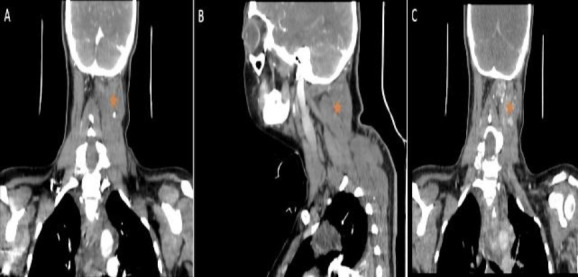

Case report: We present a rare case of a giant cervical soft tissue hemangioma with laryngeal extension in an adult female, initially misdiagnosed as a primary laryngeal hemangioma. This case underscores the critical role of diagnostic imaging in assessing the extent of these vascular tumors.

Introduction: Soft tissue hemangiomas are among the most prevalent soft tissue tumors and can pose diagnostic challenges due to their propensity to extend into various regions. In our case, imaging studies facilitated effective characterization of the mass, and timely intervention with sclerotherapy enabled adequate initial control of the lesion. Subsequently, medical management with propranolol and a second scheduled surgical intervention with sclerotherapy contributed to a reduction in the lesion size, alleviation of symptoms, and improvement in prognosis.

Conclusions: A thorough assessment of the suspected site, as well as the entire head, neck, and chest, should be conducted for all patients with suspected hemangiomas.